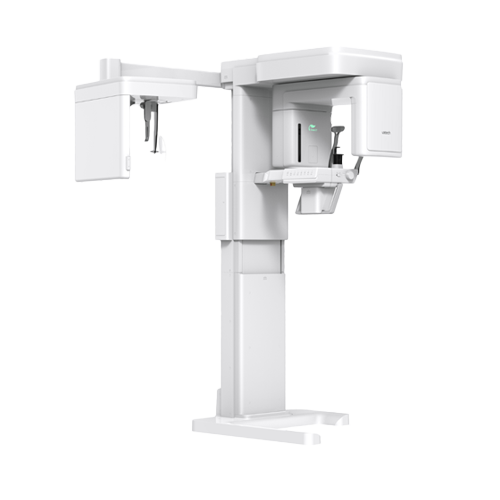

- Digital Optimum

- 진단부터 진료까지, 디지털 시스템 구축

- 오차를 줄인 정밀하고 완성도 높은 진단과 치료가 가능합니다

- 200 DENTAL CLINIC